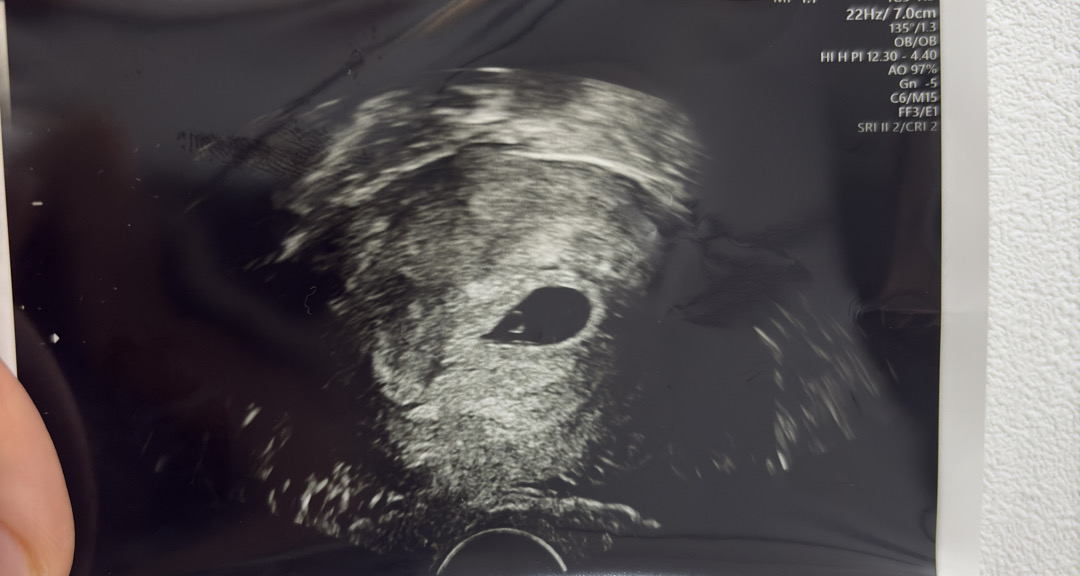

5주3일차 피고임...

오늘 병원 다녀왔는데용... 피고임이 있다고 유산끼가 보인다고 하시네요ㅠㅠ 질정 받아오고 최대한 푹 쉬라고 하셨는데... 괜찮겠죠...? 너무 걱정이네요...